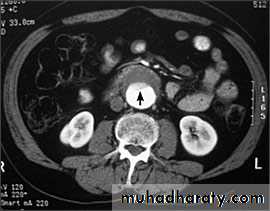

CT & CT angio of abdominal aortic aneurysm